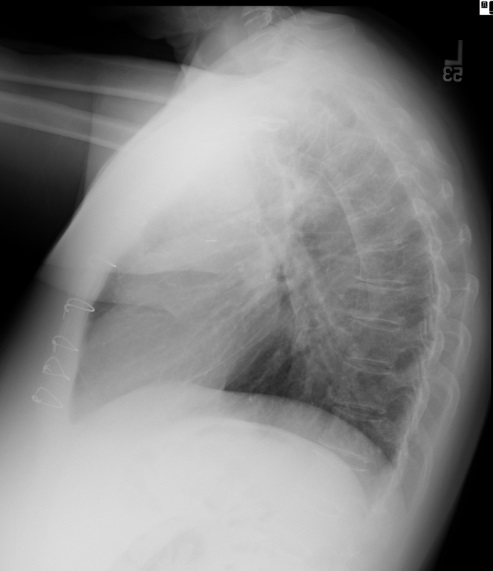

1.5 liters of serous, odorless fluid was removed and the echo appearance normalized, showing only trace pericardial fluid and a well-preserved ejection fraction. However, within four weeks the effusion re-accumulated as shown in the CXR (Fig.2) and echo showed early tamponade.